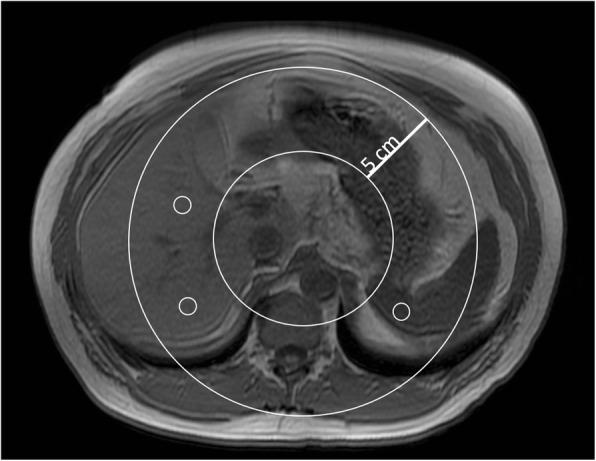

This retrospective study was approved by the institutional review board with a waiver for informed consent. We reviewed the MRI studies of 50 cancer patients (30 males, 20 females, 50-78 years old) whose exams included (1) T1-in-and-out-of-phase, (2) IDEAL-IQ, and (3) T2* mapping. Two readers independently assessed fat and iron content from conventional and IDEAL-IQ MR methods. Intraclass correlation coefficient (ICC) was estimated to evaluate agreement between conventional MRI and IDEAL-IQ in measuring R2* level (a surrogate for iron level), and in measuring fat level. Agreement between the two readers was also assessed. Wilcoxon signed rank test was employed to compare iron level and fat fraction between conventional MRI and IDEAL-IQ.

本回顾性研究经机构审查委员会批准,豁免知情同意。我们回顾了 50 例癌症患者(30 名男性,20 名女性,50-78 岁)的 MRI 检查,这些检查包括(1)T1 同相位和反相位,(2)IDEAL-IQ,和(3)T2* 映射。两位读者分别从常规和 IDEAL-IQ 磁共振方法评估脂肪和铁含量。采用组内相关系数(ICC)评估常规 MRI 和 IDEAL-IQ 测量 R2*水平(铁水平的替代物)和测量脂肪水平的一致性。还评估了两位读者之间的一致性。采用 Wilcoxon 符号秩检验比较常规 MRI 和 IDEAL-IQ 之间的铁水平和脂肪分数。